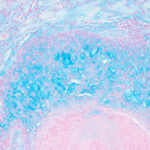

The mucin found in these six diseases represents an increase in the mucin that is normally present in the ground substance of the dermis. It consists of proteins bound to hyaluronic acid (hyaluronan), which is an acid mucopolysaccharide or glycosaminoglycan. As a result of the great water-binding capacity of hyaluronic acid, dermal mucin contains a considerable amount of water. This water is largely removed during the process of dehydration of the specimen; consequently, in routine sections, the mucin, because of its marked shrinkage, appears largely as threads and granules. |

The mucin present in the six types of mucinosis stains a light blue in sections stained with H&E. It also stains with colloidal iron. It is Alcian blue-positive at pH 2.5 but negative at pH 0.5 and shows metachromasia with toluidine blue at pH 7.0 and 4.0 but no metachromasia below pH 2.0 . It is PAS negative (indicating the absence of neutral mucopolysaccharides) and aldehyde fuchsin negative (indicating the absence of sulfated acid mucopolysaccharides). The mucin is completely removed on incubation of histologic sections with testicular hyaluronidase for 1 hour at 37″C . |